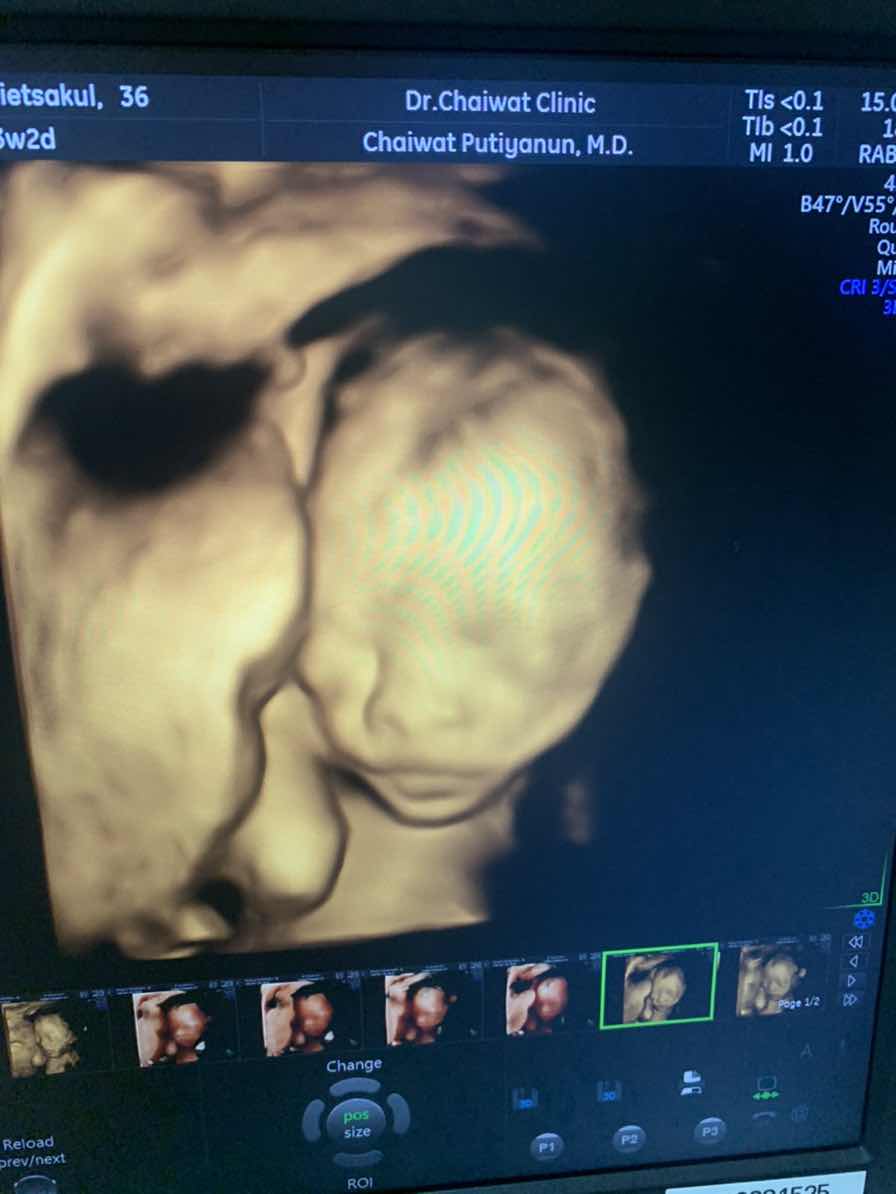

28weekจ้า

28 w จ้า